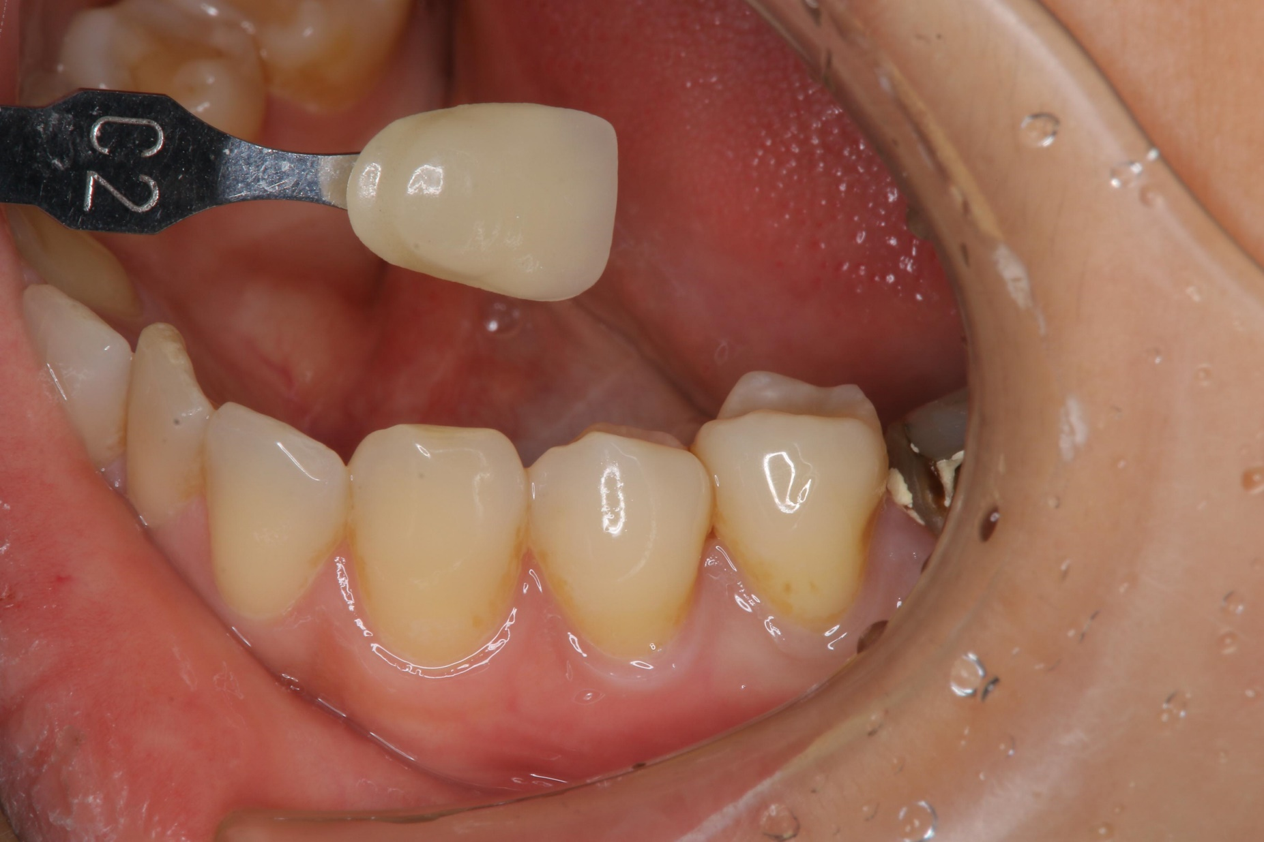

臨床照相比色